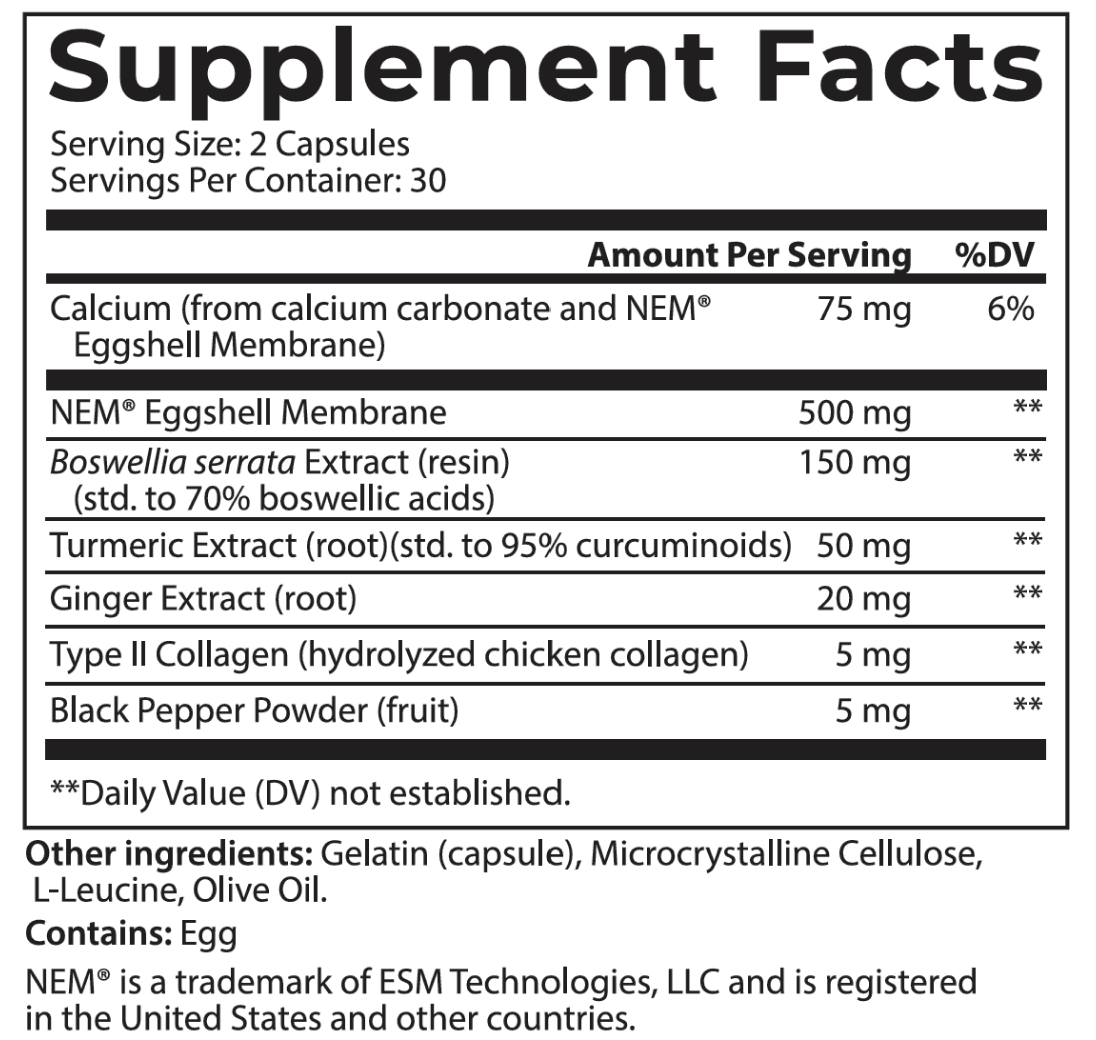

And to be 100% transparent, I’d like to show you the label that appears on every jar we ship.

Joint Support is an excellent addition to your daily routine…

And it’s so easy to use.

Simply take two capsules daily and that’s it.

In just a couple of seconds, you’ll take a huge step towards better joint health.

Personally, I recommend you take it first thing in the morning, like a daily multivitamin so you always remember to take it.